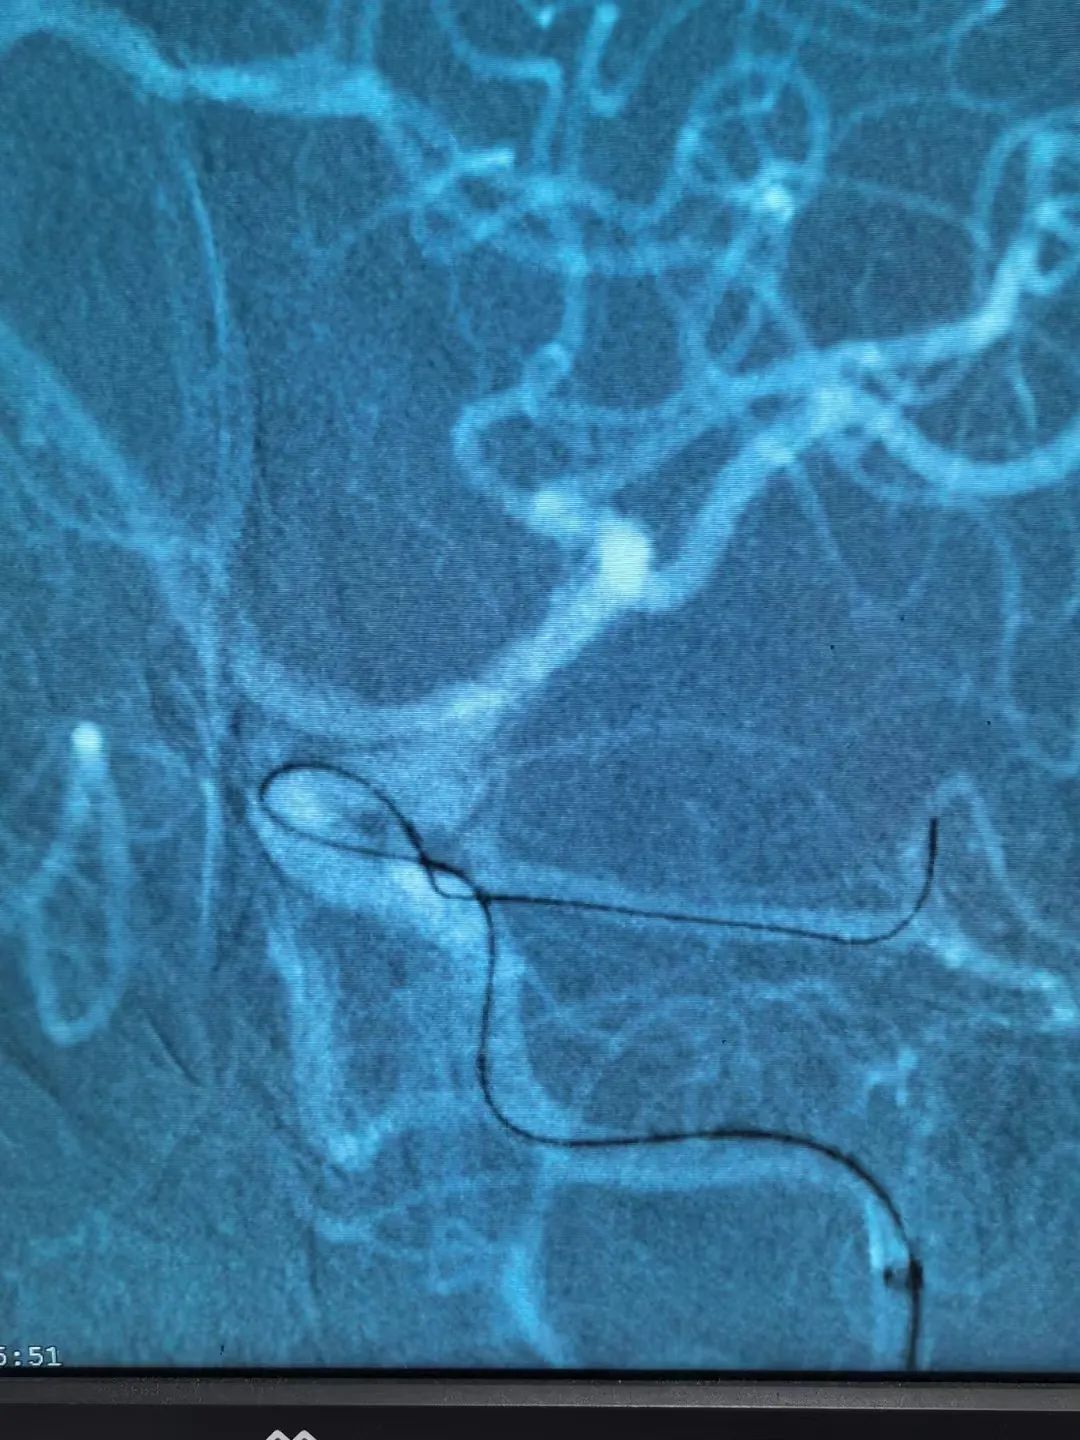

得知病情后,患者家屬非常擔(dān)心,施宏飛主任與家屬耐心溝通,并建議立即行血管內(nèi)栓塞介入治療術(shù),不然動(dòng)脈瘤隨時(shí)有可能再次破裂出血威脅生命!家屬同意后,完善術(shù)前相關(guān)檢查,在全麻下行全腦血管造影術(shù)+左側(cè)后交通動(dòng)脈瘤栓塞術(shù)。術(shù)中施宏飛主任和王明義副主任醫(yī)師通力協(xié)作,在麻醉科、介入科醫(yī)護(hù)技團(tuán)隊(duì)的密切配合下,用縝密的治療方案、精湛的介入技術(shù)成功為患者“拆除炸彈”!

1、介入栓塞:通過(guò)股動(dòng)脈插管,在DSA機(jī)器引導(dǎo)下將細(xì)小的導(dǎo)管系統(tǒng)經(jīng)過(guò)血管送達(dá)顱內(nèi),把彈簧圈填入瘤腔,達(dá)到防止再出血的目的,是微創(chuàng)治療手段。